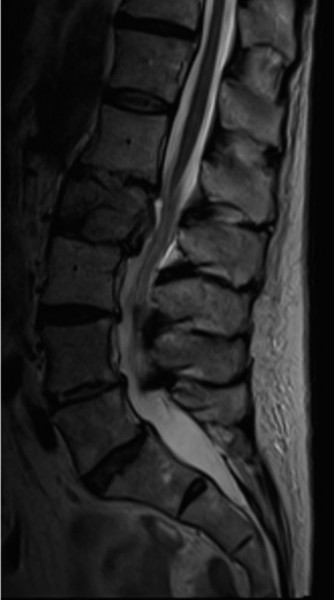

To evaluate the neural elements and the soft tissue structures, a comprehensive MRI of the lumbar spine without contrast was obtained. The T2-weighted sagittal and axial sequences confirmed the Grade 2 anterolisthesis and demonstrated severe bilateral foraminal stenosis at L5-S1. The exiting L5 nerve roots were severely compressed between the hypertrophied, fibrocartilaginous pseudarthrosis tissue of the pars defect dorsally, and the bulging, degenerated L5-S1 disc and superior endplate of S1 ventrally. Furthermore, the MRI revealed Modic Type II changes (fatty replacement of the subchondral bone marrow) in the adjacent vertebral endplates, confirming chronic biomechanical stress and discogenic degeneration. The central canal remained relatively patent, which is characteristic of isthmic spondylolisthesis, as the posterior neural arch is left behind during the anterior translation of the vertebral body.